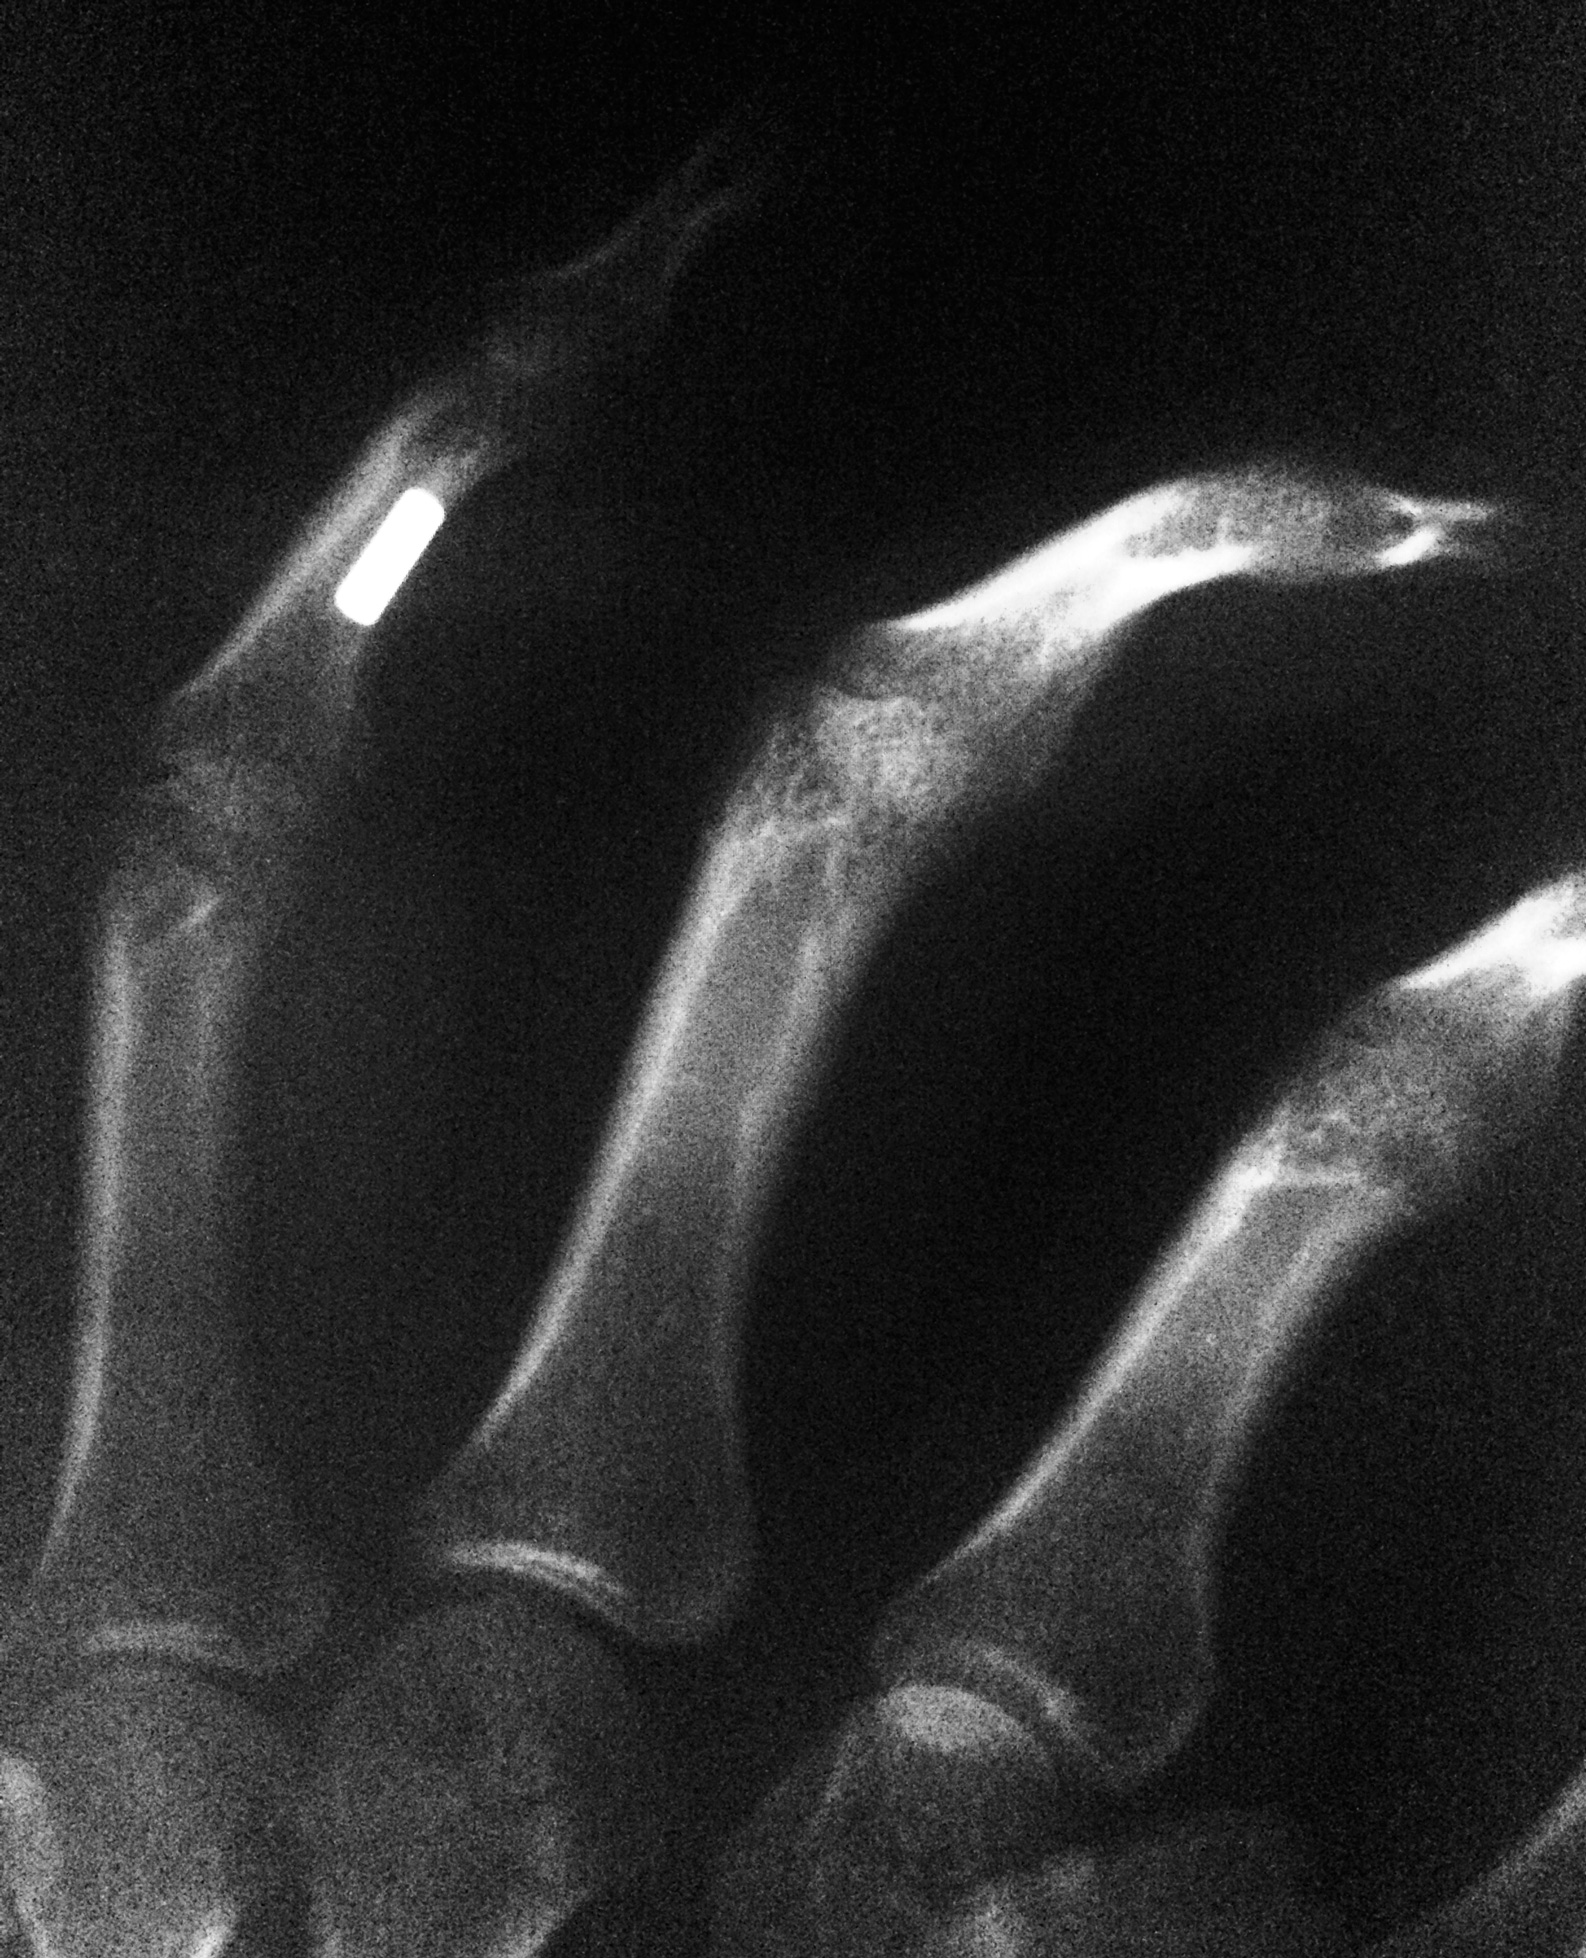

It's a small neodymium magnet that's on the left-side of the "middle-part" of my left-hand's ring-finger. I don't know the exact measures, but I'd say it's about 2mm thick.